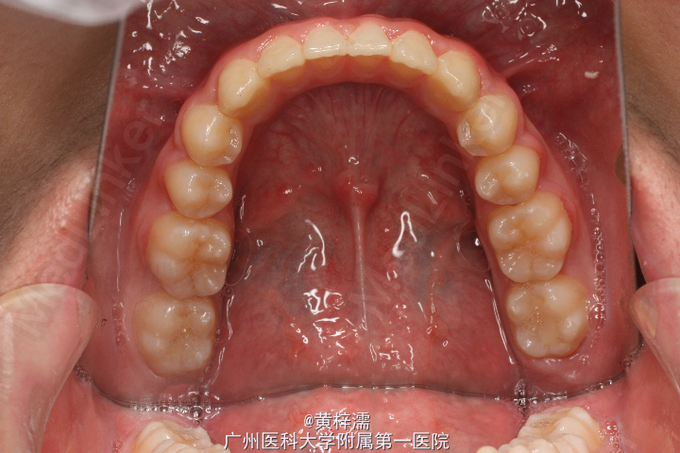

面部基本对称,无露龈笑,笑容不自然。直面型,面中1/3高度与面下1/3高度基本相等。下颌后缩,颏部发育稍不足。上中线与面中线一致,下中线稍右偏0.3mm。左侧磨牙关系中性,无尖牙关系。22,24间前庭沟下方可见鼓起,扪及23,磨牙覆盖正常。右侧磨牙关系中性,尖牙关系1/4远中,磨牙覆盖正常。上牙弓卵圆形,23缺牙间隙8.5mm,13宽度为8.5mm。口腔卫生可,未见牙体、牙周疾病,颞下颌关节检查未见异常。

诊断:安氏ǀ类错牙合;23埋伏阻生牙 处理:选择非拔牙矫治+23外科-正畸导萌术。全口固定正畸治疗,排齐阶段使用双丝技术牵引23,精细调整咬合关系及保持,总疗程18个月。

患者对治疗效果满意,拆除保持器维持1年。讨论:在判断阻生尖牙是否能自行萌出首先需判断阻生牙的倾斜角度及与侧切牙重叠位置,一般阻生超过侧切牙牙根1/2的阻生牙较难自行萌出,第二需要观察尖牙牙根发育状况而定。本患者尖牙已无自行萌出的趋势,因此行正畸牵引。 处理此类阻生尖牙时,首先粘接牵引附件需要确定牵引方向,控制牵引过程牙根不能碰及邻牙;其次牵引阻生牙时,牙列主弓丝必须时硬丝,利用短NITI丝段对阻生牙进行牵引,这样可以避免牵引过程对邻牙产生影响,稳定牙弓。第三,牵引后需要观察牙根方向和轴向,如不佳需要调整为好。